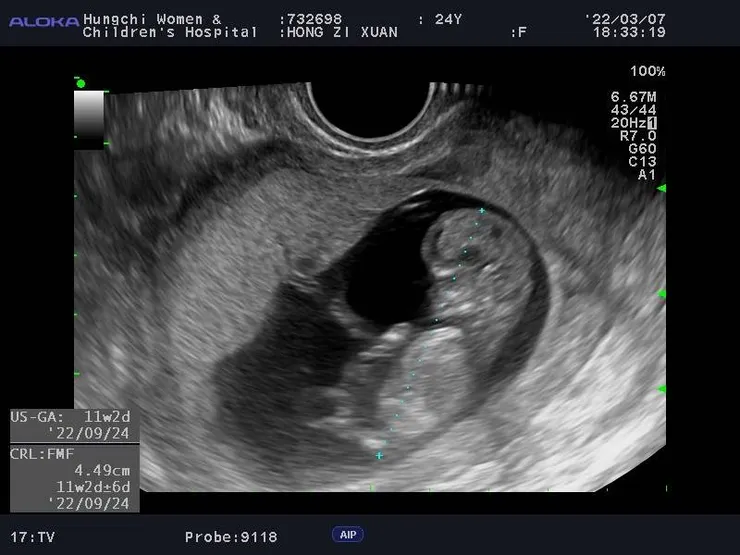

這個故事要從我懷孕過程開始,在我發現自己懷孕的時候小寶寶已經滿三個月了,在懷孕的這三個月,我每個月都有規律的出血,我以為是生理期,也沒有多想,這三個月我們公司還集體被抓去嘉義隔離,當時我身體就很虛一直再吃感冒藥,解隔離後身體一直很不舒服我就跑去整骨,這期間我還出車禍還要X光,直到三月的某一天,突然覺得好像要驗孕一下!咦!?結果兩條線!

我就這樣發現了老天的禮物,告訴了大家這個件事,大家的表情都很驚訝,其實我自己也很驚訝!他們的第一個反應是,你這個三個月發生了這麼多奇妙的事,居然小孩還在,還很健康,哇!這個小孩真的就是要跟你!